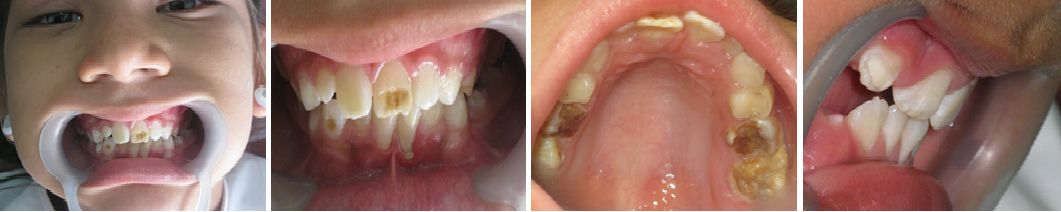

- MANEJO DE LA CARIES DE LA INFANCIA TEMPRANA

Esta es una de las problemáticas de salud pública que de manera desafortunada no tiene programas de atención de amplia cobertura por la complejidad de su manejo integral.

Los pacientes que son afectados por esta entidad siempre son de difícil manejo, tanto en lo comportamental como en la dificultad propia de la rehabilitación necesaria para cada caso especial.

MASIVAS DESTRUCCIONES DE LAS CORONAS DENTALES POR CARIES EN LA DENTICION TEMPORAL.

Esta entidad requiere siempre tratamiento direccionado y ejecutado por especialista en Odontología Pediátrica, cuya formación y experiencia permitan desarrollar los cambios en el contexto familiar y la eliminación de focos sépticos y rehabilitación correspondiente necesaria en estos pacientes.